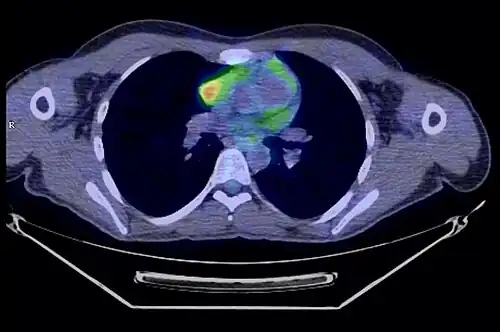

La place du TEP scanner dans le diagnostic des thymomes est encore débattue[31]. S'il existe bien une hyperfixation de la tumeur, son rôle dans le diagnostic de l'extension locorégionale reste à préciser[33].

- Thymome de type B1 en TEP scanner

Coupe transversale. Les trois clichés sont extraits du même examen.

Coupe frontale ; la tumeur est à l'intersection des lignes rouges.

Coupe sagittale ; la tumeur est à l'intersection des lignes rouges.